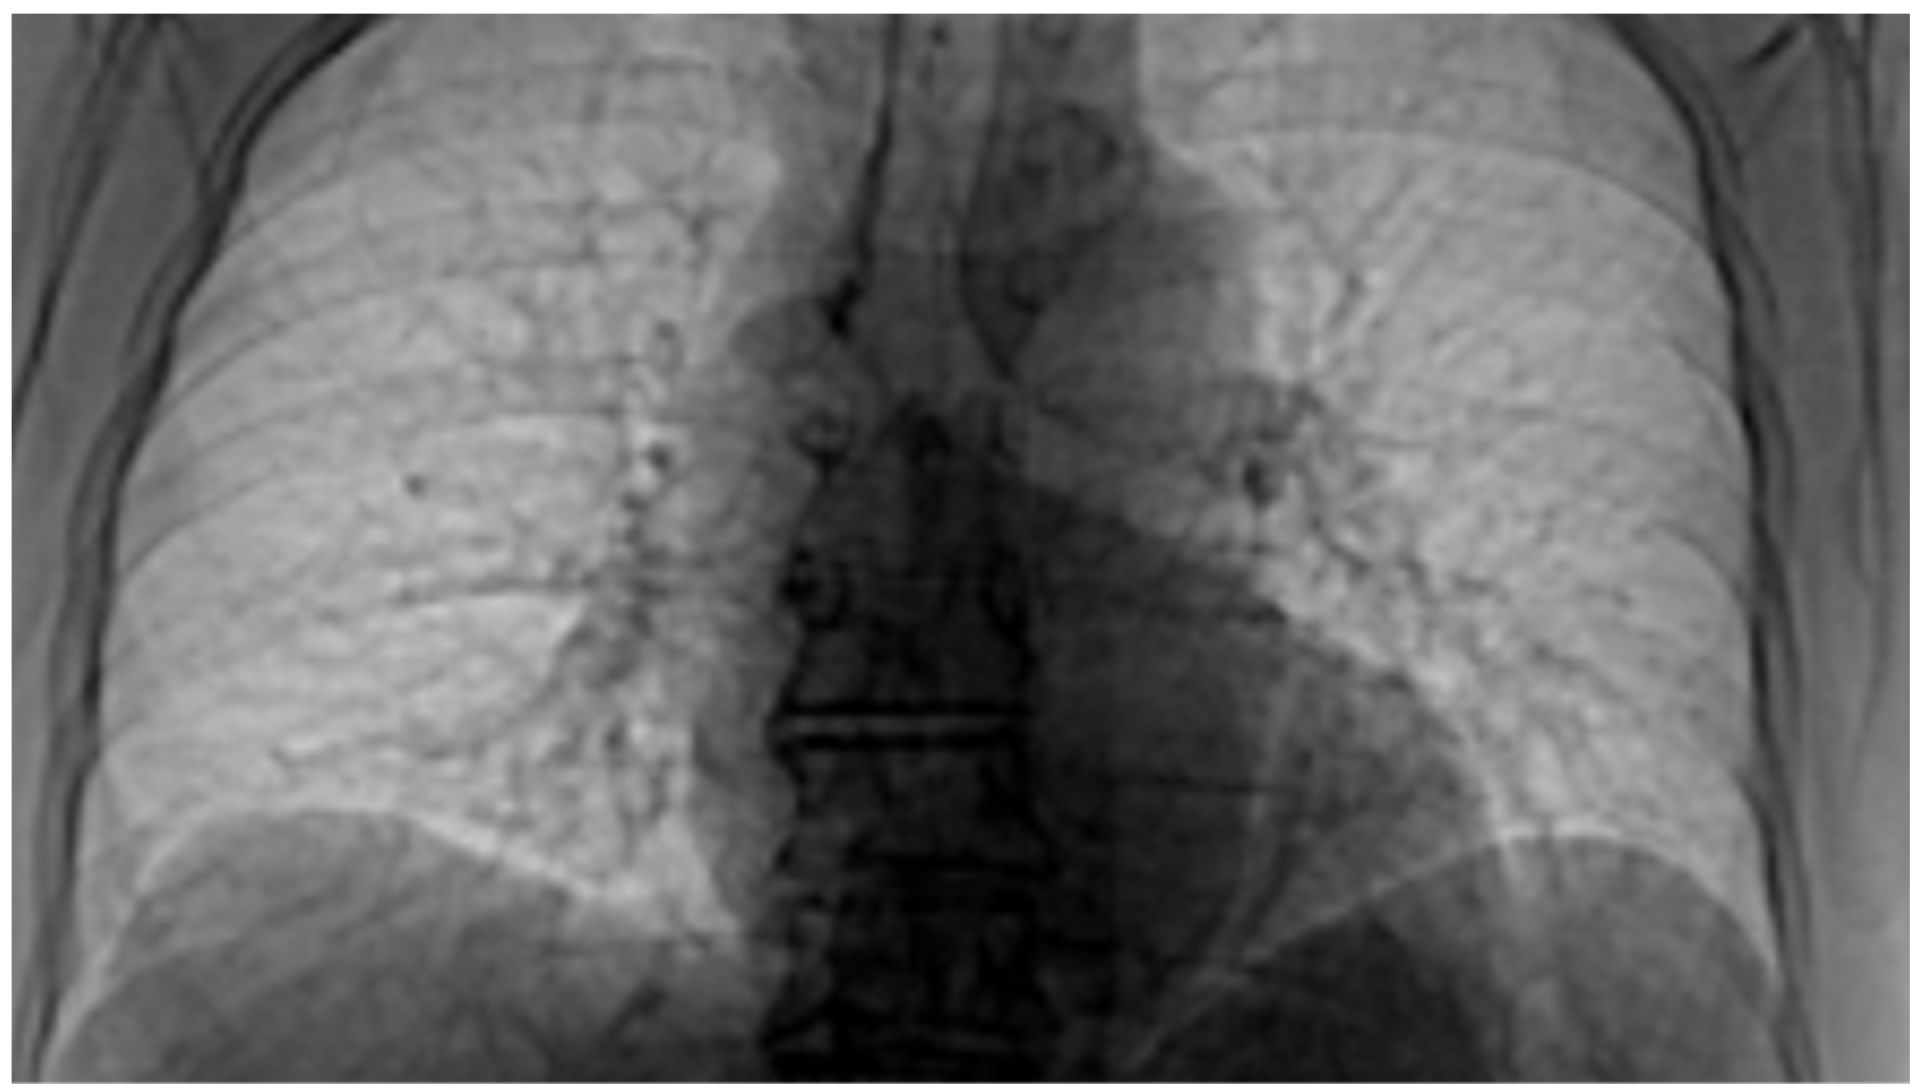

3.3. Patient Code: VU

Date of performing the pulmonary investigation: 26 February 2021.

Figure 12 and Figure 13 show the selection of lung portion of interest for patient 3 (VU) and the same image in “Invert color” format.

Figure 14 and Figure 15 present the defined masks for the left lung and right lung, framed in blue borders.

Table 3 shows the known fractal indicators, such as the fractal dimension of the CT image of the left lung, d1L = 1.8836 ± 0.3148m, and the lacunarity, Λ = 0.0279; and the fractal dimension of the right lung, d1R = 1.8772 ± 0.3204, and the lacunarity, Λ = 0.0291.

Figure 16 shows the 3D graphical representation of voxels contained in patient VU’s CT lung image.